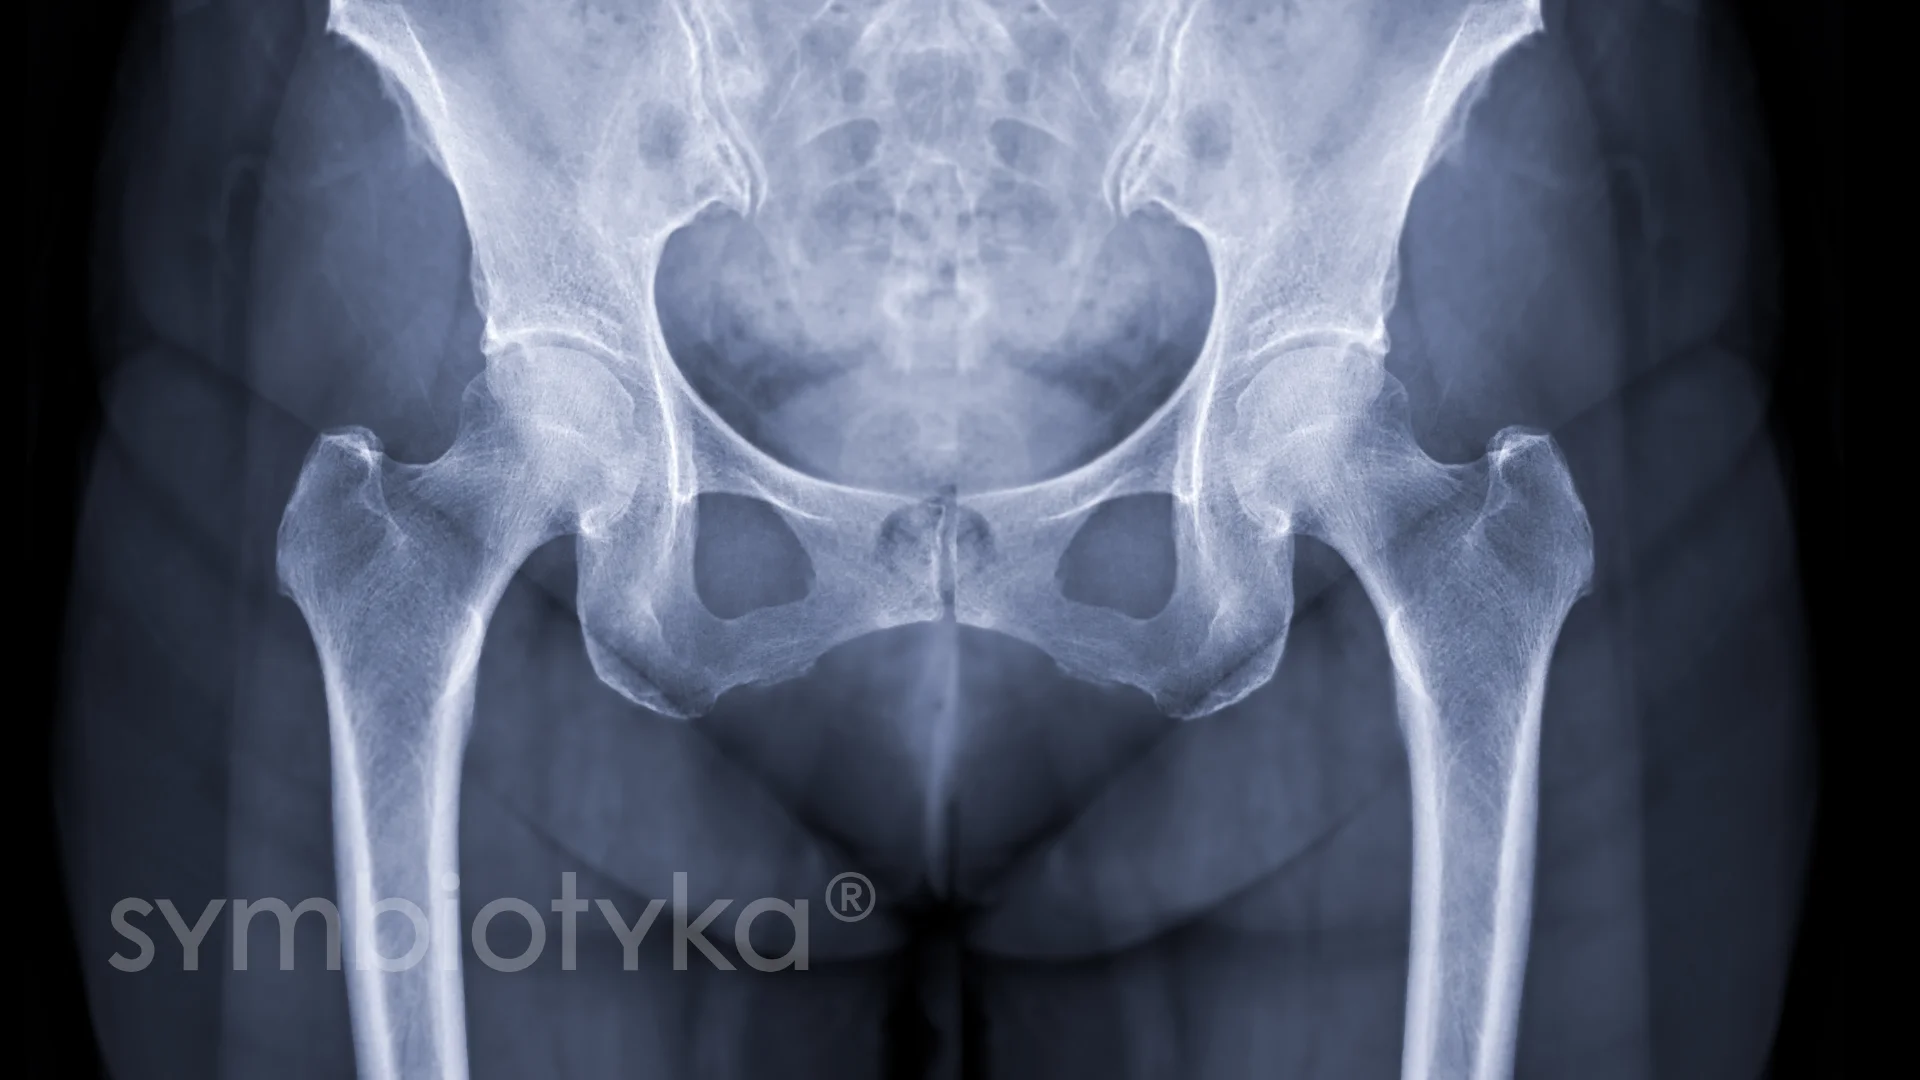

Ендопротезування кульшового суглоба — це сучасна ортопедична операція, під час якої пошкоджені або зношені частини тазостегнового суглоба замінюють на штучні імпланти. Така методика дозволяє усунути хронічний біль, повернути свободу рухів та відновити активність пацієнта у повсякденному житті.

Кульшовий суглоб є одним із найбільших і найважливіших у тілі людини, адже саме він відповідає за підтримку ваги тіла, ходу та більшість рухів нижніх кінцівок. Проте травми, вікові зміни, артроз чи інші захворювання поступово руйнують його структури та обмежують рухливість.

Кульшовий суглоб є одним із найбільш навантажених у людському організмі, адже він бере участь у ходьбі, бігу, сидінні та стоянні. Постійний тиск ваги тіла, травми чи хвороби поступово можуть руйнувати його структури, викликаючи біль, обмеження рухливості та потребу в серйозному лікуванні.